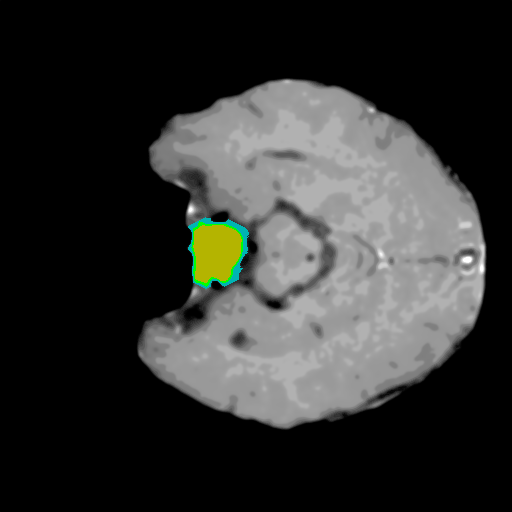

Extensive experiments have been performed in the current setup, and experimental outcomes are reported with the demonstration of numerical and statistical analyses using the proposed QFS-Net, QIS-Net [39], convolutional U-Net [18] and Residual U-Net (URes-Net) architectures [20]. The human expert segmented skull-tripped contrast enhanced DSC brain MR input image slices of size and ROIs are provided in Figure 5 as samples. The demonstration of QFS-Net segmented images followed by the essential post-processed outcome on the slice no. for class level with four distinct activation schemes () are shown in Figure 6. It is evident from the experimental data provided in Table LABEL:tab1 that the proposed QFS-Net performs optimally for the -connected quantum fuzzy pixel information heterogeneity assisted activation () with and gray scale set in comparison with other thresholding schemes and gray scale sets under the four evaluation parameters () [44]. The segmented tumors obtained using the proposed self-supervised procedure under class transition levels with four different thresholding schemes , , and are demonstrated in Figures 7- 8 for the class boundary sets and [39], respectively. The segmented images using the remaining two class boundary sets ( and ) [39] are provided in the supplementary materials section. The segmented ROIs describing the whole tumor region after the masking procedure using QIS-Net, U-Net and URes-Net are also reported in Figure 9.